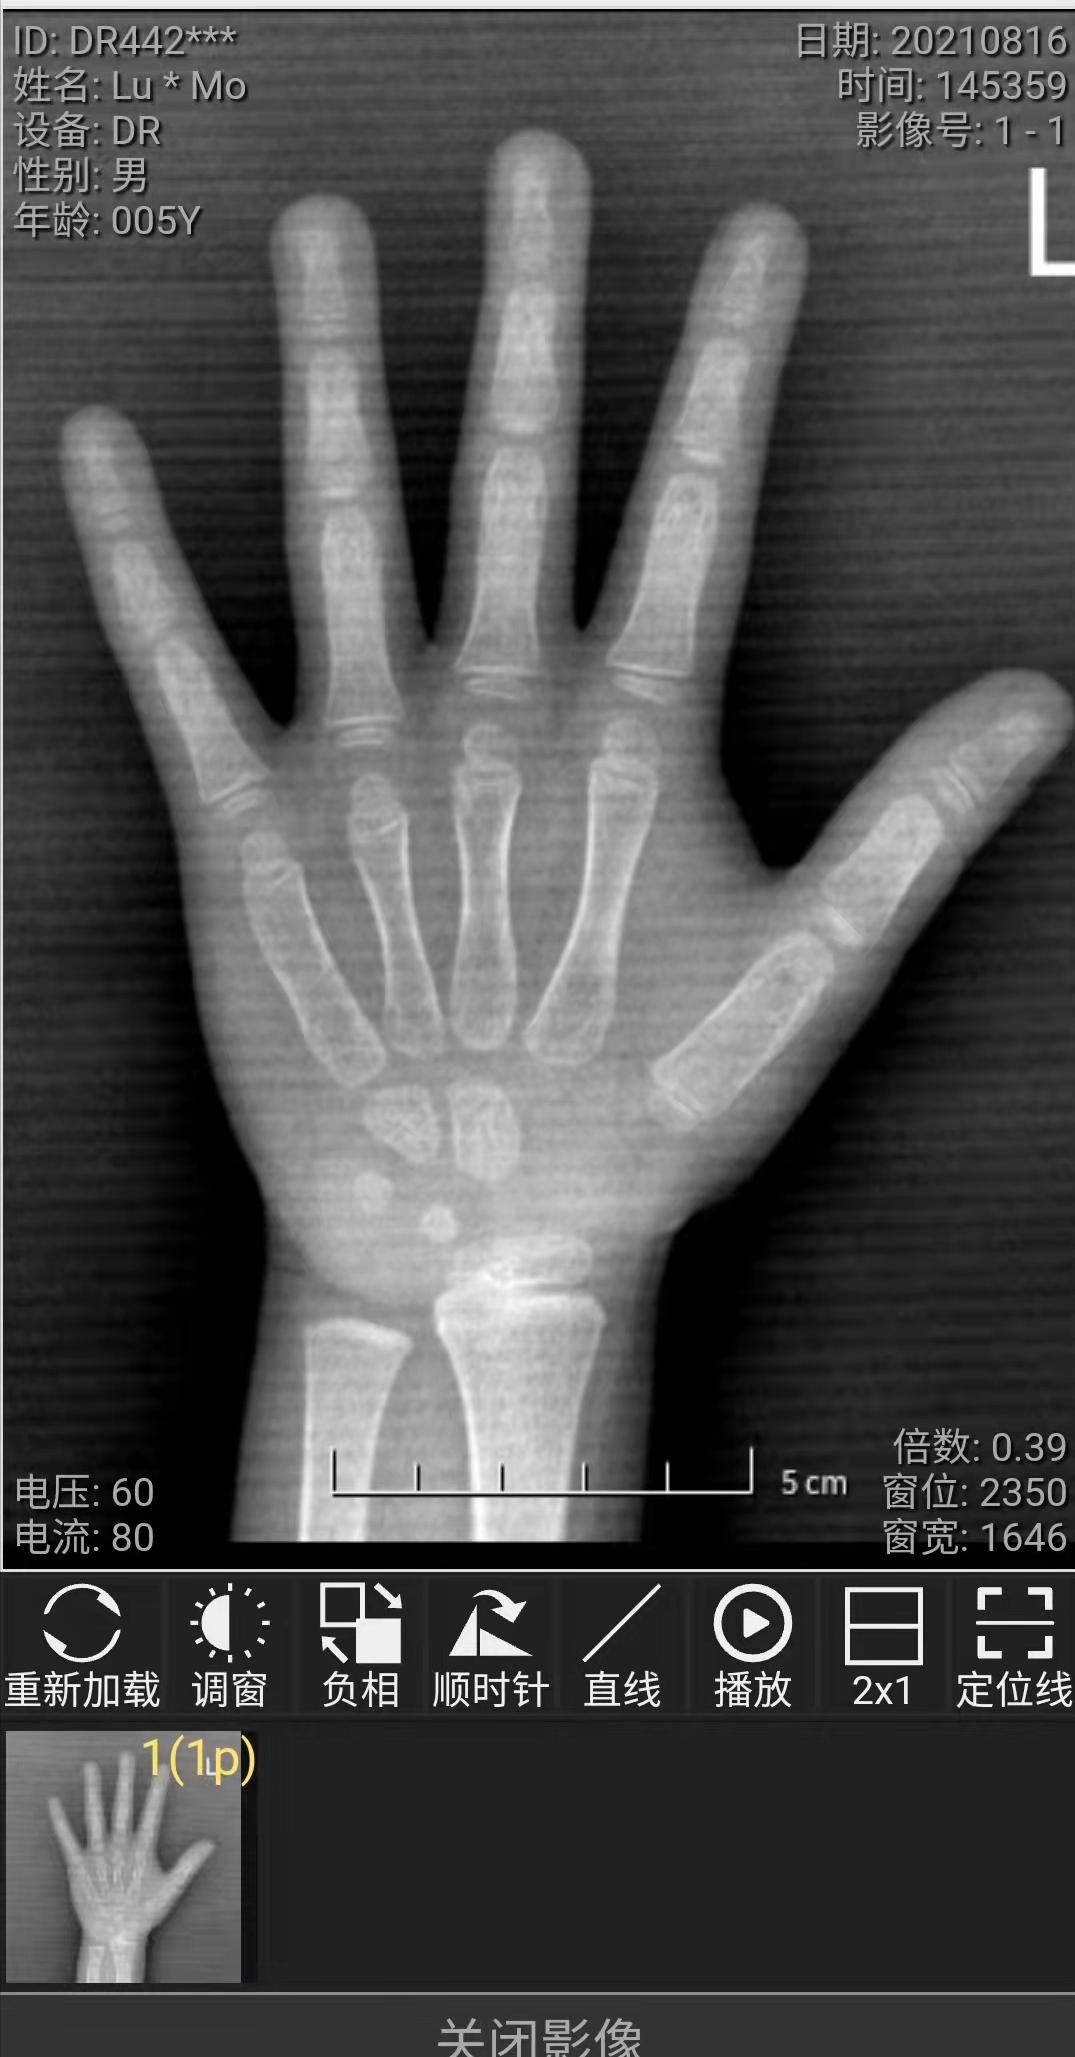

评估骨龄一定要看的是骨龄原片

最多的问题还是不清晰,点开每块骨头模糊一片

因为骨龄评估是通过计算每一块骨头的等级,看不清楚根本没法评,硬评误差往往会比较大。

正确拍骨龄片很重要,直接影响到骨龄评估的准确度 ,别说差1岁了,差半岁就是3-4厘米的身高,结果有可能是完全不一样的。

比如一个5岁的男孩,身高102,评估4.5岁的骨龄,孩子生长曲线在10百分位,评估5岁的骨龄,就是矮小症水平, 下一步要怎么做,给的干预方案完全不一样。